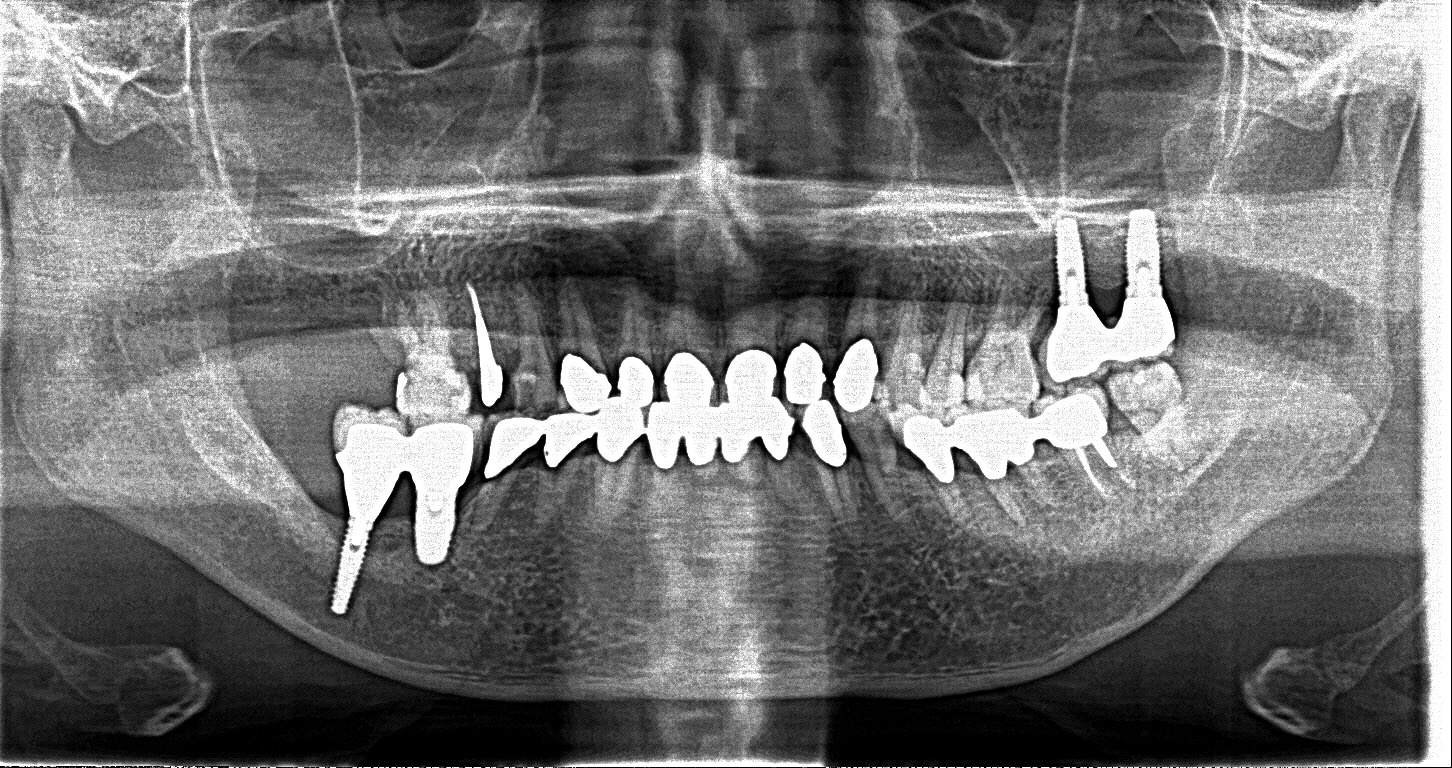

この患者様は、右上の奥歯の歯茎から出血してくるとのことで来院されました。歯周組織検査とレントゲンで診断を行った結果、重度の歯槽膿漏が認められ、保存不可能の為、抜歯になると伝えたところ、入れ歯は絶対に嫌だと言われたので、インプラント治療となりました。CT撮影を行ったところ、上顎洞底までの距離が3ミリ程度しかなかったのですが、骨が固く、フィクスチャーの一次固定が良好だったので、開窓法による上顎洞底挙上術とフィクスチャーの埋入を同時に行いました。約10カ月後に二次手術を行い、上部構造をセットしました。また、右下の臼歯部のブリッジにも大きな二次カリエスが認められ、7番の遠心根が抜歯になり、6番、7番にインプラント治療をしました。